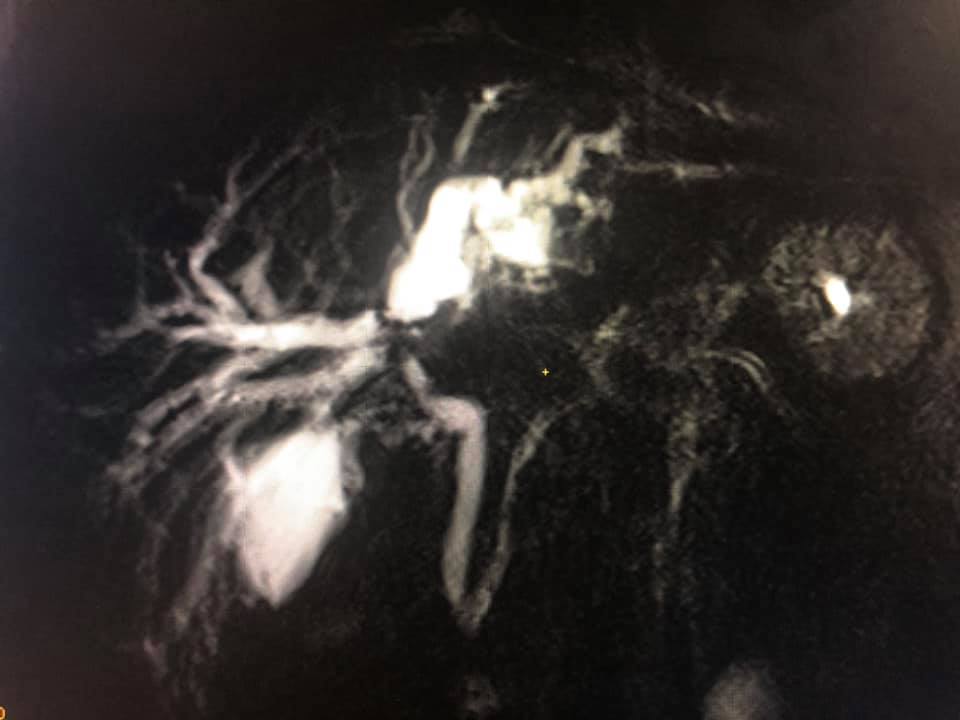

Challenging emergency during the COVID: Child’s A CLD with HUGE gastric varices uncontrolled

Child’s A CLD with HUGE gastric varices uncontrolled by Endoscopic glue and attempted EUS coiling. One salvage option would be TIPSS with balloon vascular occlusion but due to logistics we went for modified sugiura procedure. Splenectomy + Gastro esophageal devascularisation with anterior Gastrotomy and overseeing of gastric varices with pyloroplasty. Images show 1 CECT showing large gastric fundal varices. 2,3,4 Gastro Esophageal devasc 5, 6 Large fundal varices before and after oversewing. 7. Anterior gastrotomy 8. Pyloroplasty. Postoperative recovery was uneventful.